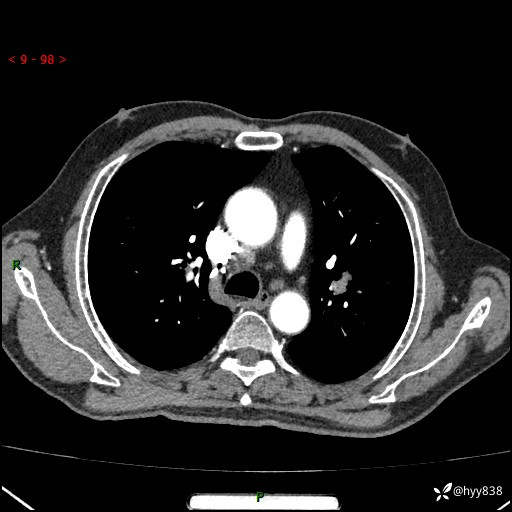

辅助检查:CT

增强